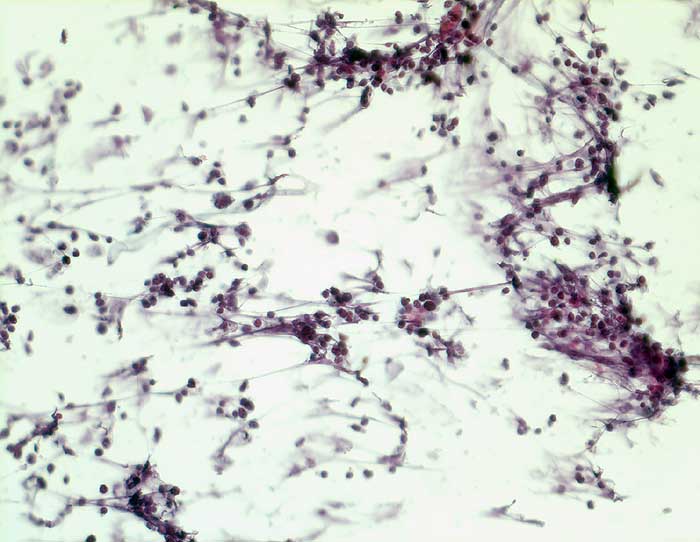

PathoPic ID 5750 - Kleinzelliges Karzinom

Kleinzelliges Karzinom

maligner Tumor

FNP, Feinnadelbiopsie

Lunge, Mediastinum mit Thymus

Feinnadelbiopsie paratracheal rechts: In lockeren Gruppen und

zeilenförmigen Verbänden liegende nacktkernige Tumorzellen mit fragilen Kernen

Grosse Raumforderung im vorderen Mediastinum und infrakarinär re mit Lebermetastasen

Zytologische Diagnose: zahlreiche Zellen eines kleinzelligen Karzinoms

Zytologie

200